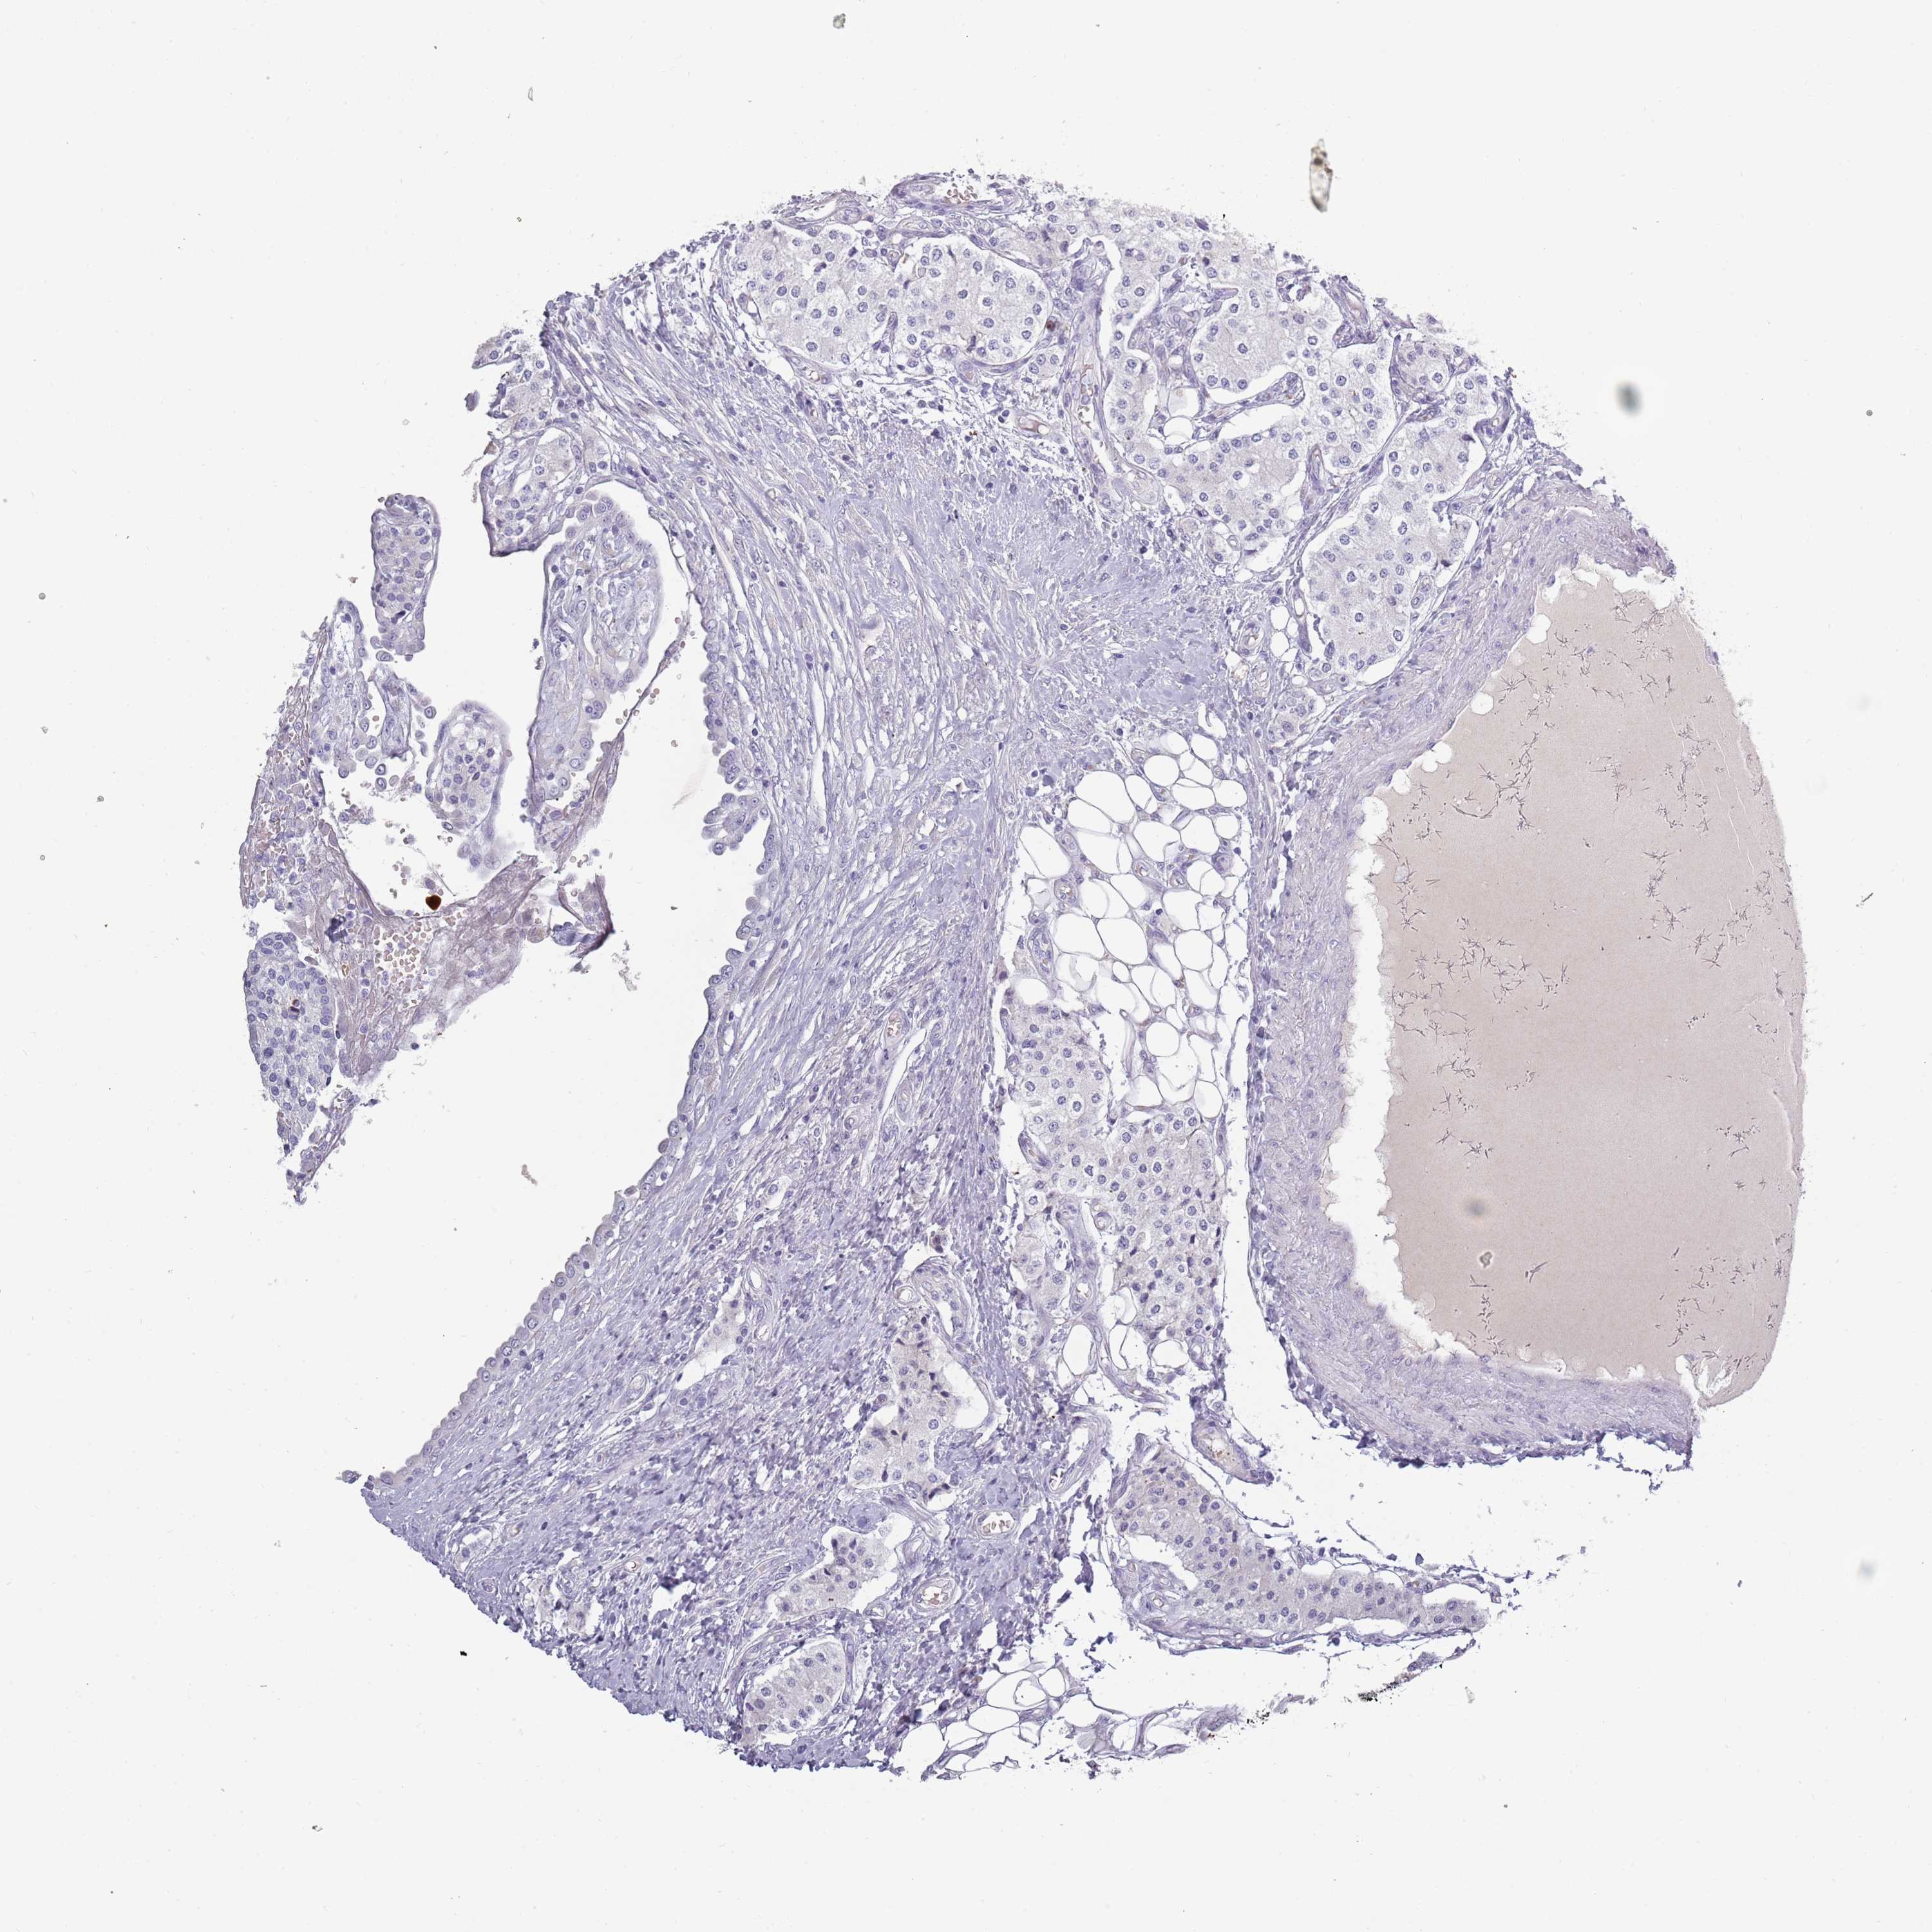

CARCINOID - Protein expressioni

A mouse-over function shows sample information and annotation data. Click on an image to view it in a full screen mode. Samples can be filtered based on level of antibody staining by selecting one or several of the following categories: high, medium, low and not detected. The assay and annotation is described here.

Antibody stainingi

Antibody staining in the annotated cell types in the current human tissue is reported as not detected, low, medium, or high, based on conventional immunohistochemistry profiling in selected tissues. This score is based on the combination of the staining intensity and fraction of stained cells.

Each image is clickable and will lead to virtual microscopy that enables deeper exploration of all samples and also displays staining intensity scores, fraction scores and subcellular localization as well as patient and tissue information for each sample.

Antibody HPA047154

Carcinoid, malignant, NOS

Carcinoma, NOS